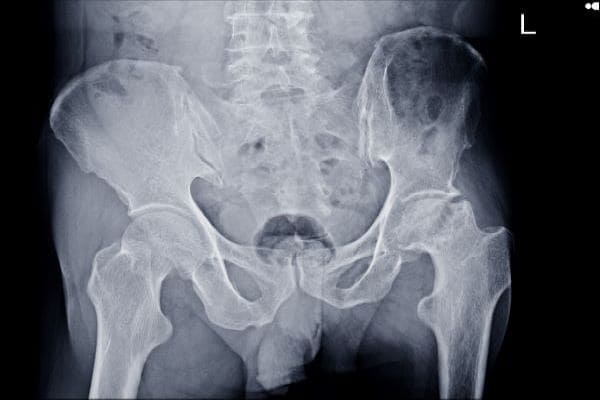

Pelvic and Acetabular Fracture Surgery

An acetabular fracture is a break in the socket portion of the “ball-and-socket” hip joints.